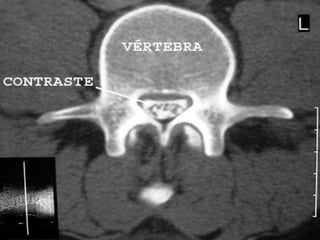

• É frequentemente realizada imediatamente após a

conclusão da mielografia enquanto o material de contraste

ainda está presente dentro do canal espinhal. Esta

combinação de estudos de imagem é conhecido como

mielotomografia.

• As relações anatômicas são mais bem visualizadas

quando os cortes de TC axiais são feitos

perpendicularmente ao eixo central do canal espinhal. O

uso de reconstrução computadorizada de imagem

consequente aos cortes tomográficos em planos frontais

ou sagitais dão orientação e resolução espacial.

• Esse exame irá acrescentar mais 15 a 30 minutos ao

tempo total do exame.